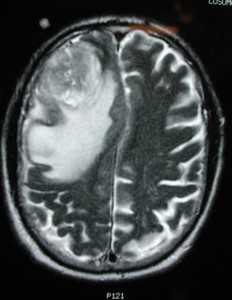

Глиобластома: симптомы, выявляемые с помощью МРТ. Аксиальный срез в режиме Т1 после контрастирования препаратом гадолиния демонстрирует распространенную опухоль правой лобной доли. Изображение предоставлено доктором George Jallo.

МРТ того же пациента. Т2-взвешенное изображение демонстрирует то же поражение, что и на предыдущем рисунке с заметным отеком и смещением срединных структур. Эти находки соответствуют высокой степени злокачественности опухоли.